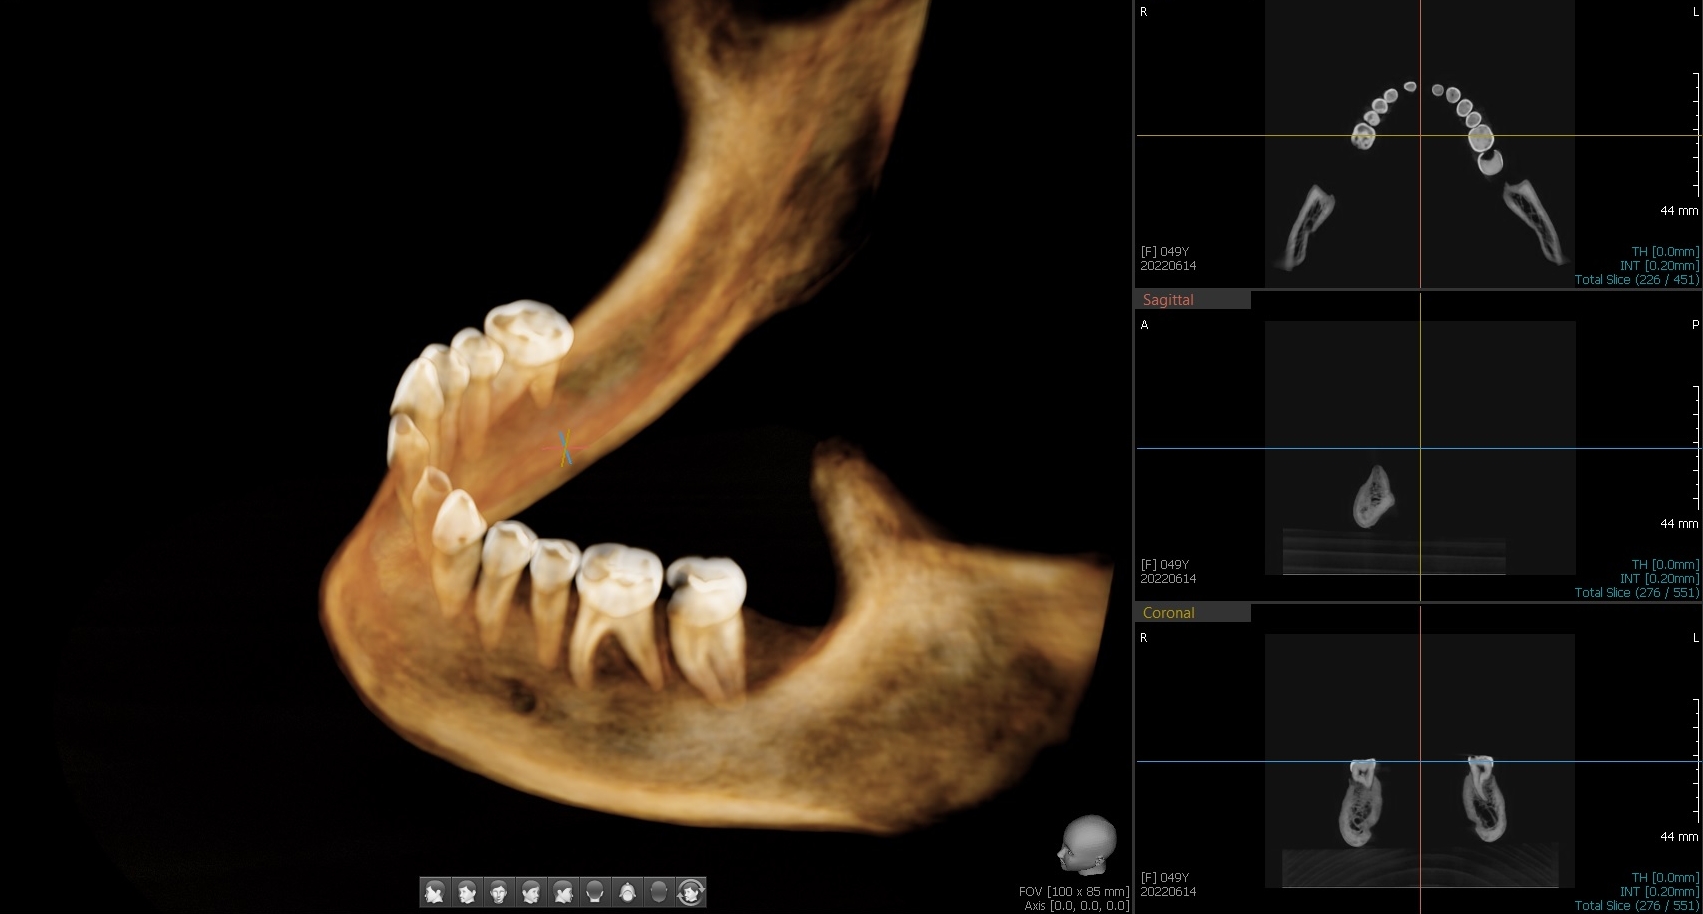

– Na przegląd stomatologiczny z Muzeum w Gliwicach zostało przekazanych 6 czaszek lub ich części, z czego 5 należało do osób dorosłych, a jedna do młodego dorosłego. Wykonaliśmy podstawowy przegląd, badanie pod kątem próchnicy (DiagnoCam), wybrane zęby były oceniane pod mikroskopem, pobrano również skany 3D i przeprowadzono cyfrową diagnostykę radiologiczną. Każdy z „pacjentów” miał założoną typową kartotekę, w której zaznaczano spostrzeżenia dentystów. Całość trwała 3 intensywne dni, a po tym czasie eksponaty wróciły do Muzeum – opisuje przebieg badań lek. dent. Marta Szymańska-Pawelec, dentystka odpowiedzialna za projekt z Dentim Clinic Medicover w Katowicach.

Zęby w 3D

Cyfrowe skany 3D też dostarczyły wielu ciekawych informacji, bo okazuje się, że przynajmniej jeden aspekt zdrowia zębów raczej nie przysparzał im zmartwień – zgryz.

– Raczej nie musieli chodzić do ortodonty. W tych przypadkach, w których mieliśmy taką możliwość, czyli były zachowane szczęka i żuchwa, stwierdzaliśmy prawidłowe warunki zgryzowe (zgryz eugnatyczny). To również może być zasługą diety. Żucie i gryzienie twardych, włóknistych produktów sprzyja prawidłowemu rozwojowi kości szczęki oraz żuchwy, a tym samym właściwemu ustawieniu się zębów. Nie bez znaczenia może być też fakt braku smoczków dla dzieci, które – zbyt długo używane – sprzyjają wadom zgryzu. Dzieci wtedy karmiono piersią, a dieta nie zawierała aż tylu miękkich, papkowatych produktów – zauważa ekspertka.